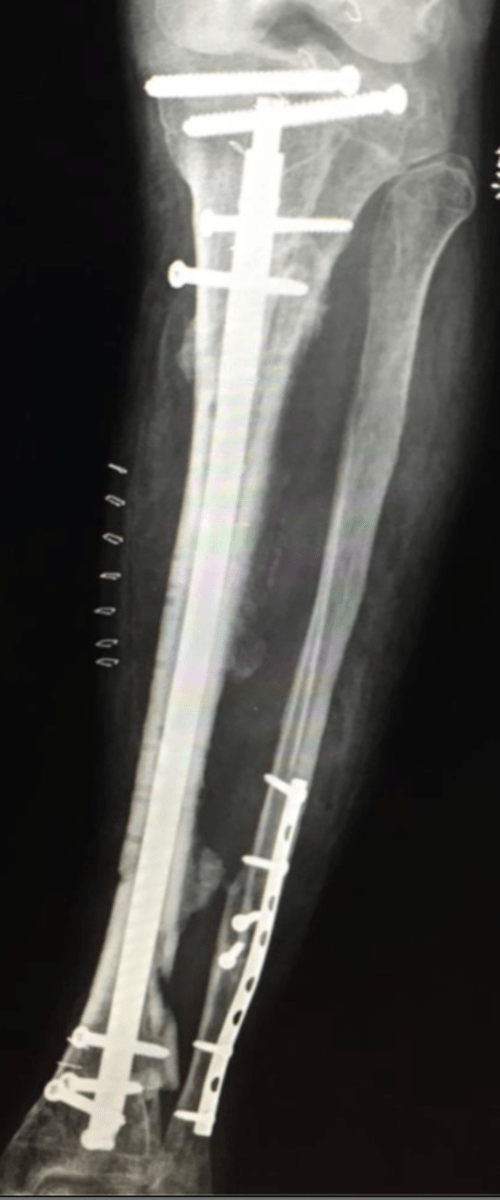

We will operate as first assist with the chief of trauma as well as other orthopaedic faculty and see patients in clinic. In addition to acute trauma, residents will also operate on complex trauma and subspecialty cases including chronic nonunions and malunions, limb deformity and salvage.

During our two weeks in Santiago, Chile we interacted with residents, fellows and attendings at various stages of training and practice. We reviewed complex Orthopaedic trauma cases and strategies in fixation and operated in a variety of settings. Although we were able to share our "American" perspective I think it was myself and my co-resident that I traveled with that were impacted the most. We were able to experience the extremes of chilean healthcare-from patients referred from the public hospitals with chronic nonunions who had been waiting and saving for surgery for years as well as the other end of the spectrum in the private hospital with resources beyond what we have in the US.